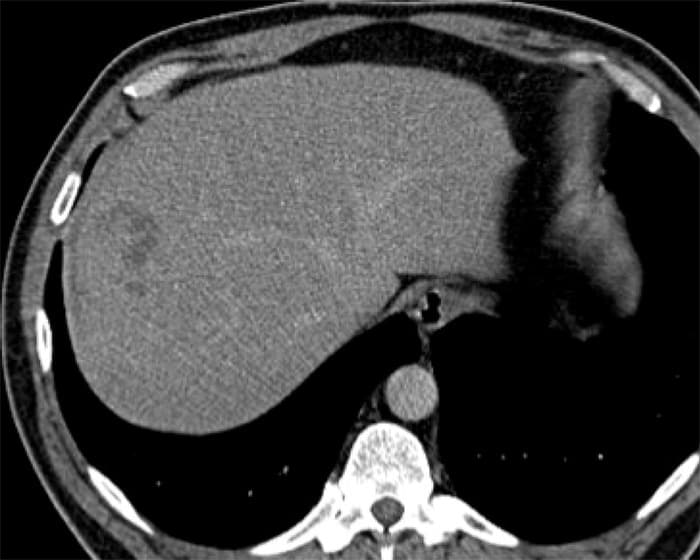

Sán lá gan

» Thông tin: Nam giới – 52 tuổi.

» Lâm sàng: Kiểm tra sức khỏe.